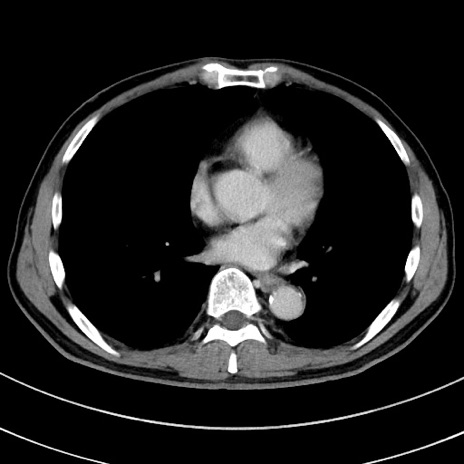

症例8(横断像)

【症例】 60歳代男性

【主訴】 黒色吐物

【現病歴】 4日前から嘔気自覚、2日前の朝食後にも嘔気あり、自分で手で嘔吐反射起こし嘔吐したところ血が混ざっていたため受診。

【既往歴】 5年前汎発性腹膜炎を伴う急性虫垂炎で手術、高血圧、前立腺肥大症、高脂血症

【身体所見】 腹部正中に手術癩痕あり 腹部平坦・軟圧痛なし膨満感あり

【データ】WBC 8400、CRP 4.54